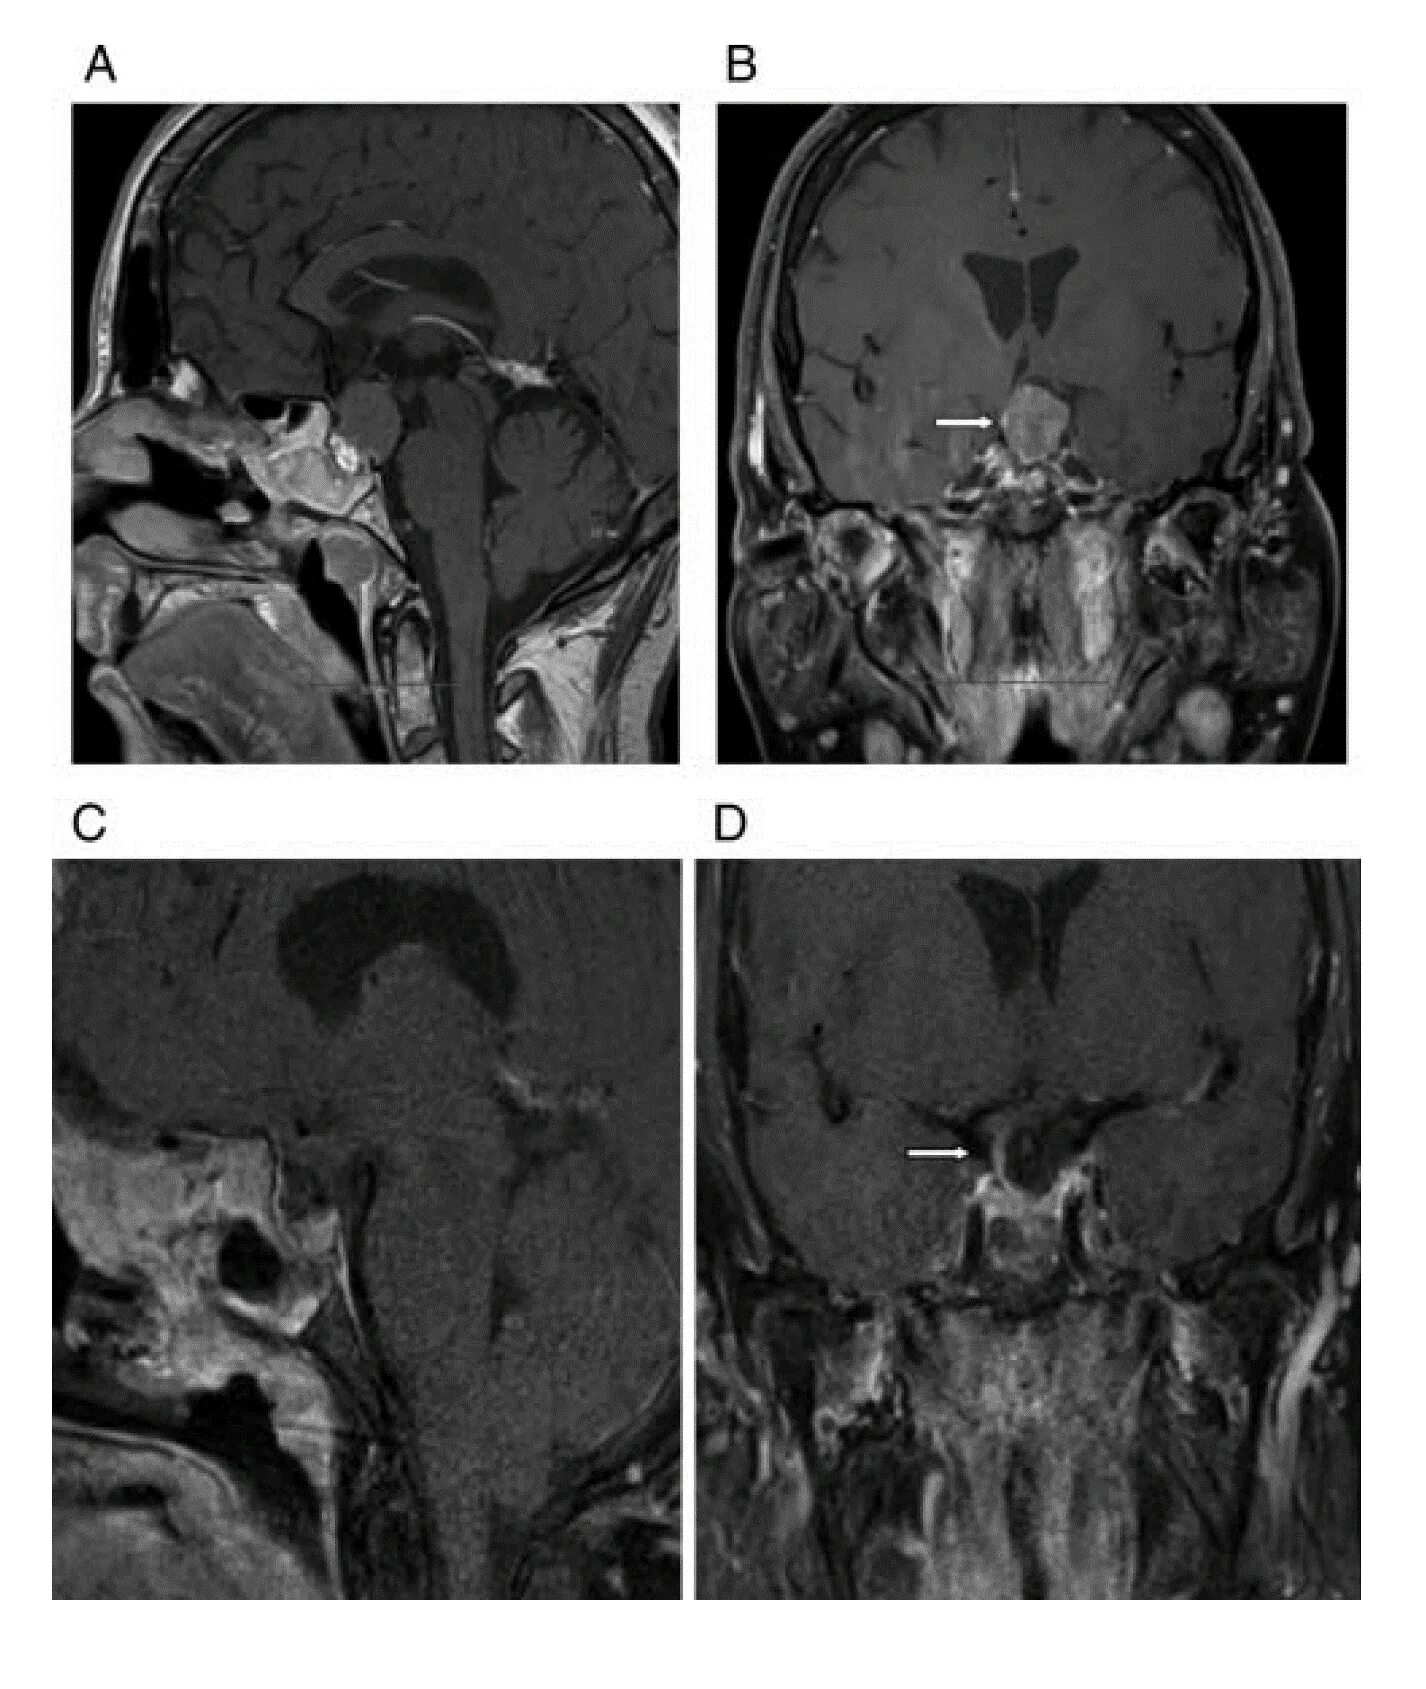

Макроаденома гипофиза